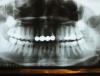

Наталья99 Опубликовано 27 марта, 2011 Автор Поделиться Опубликовано 27 марта, 2011 (изменено) отек уже прошел, возможно меня все-таки продуло. Но рот до сих пор до конца не открывается ( но есть уже могу, не очень твердое). Я была на консультации у двух врачей, все говорят, что не понимают, что у меня случилось. Во всяком случае, с нижней восьмеркой (которую удалили) проблем нет. Я сделала панорамный снимок, может кто-нибудь подскажет, что делать дальше. Потому что дискомфорт остался, Боли нет, т.е. чуть-чуть ноет. Пока мне посоветовали только ждать... Изменено 27 марта, 2011 пользователем Наталья99 Ссылка на комментарий